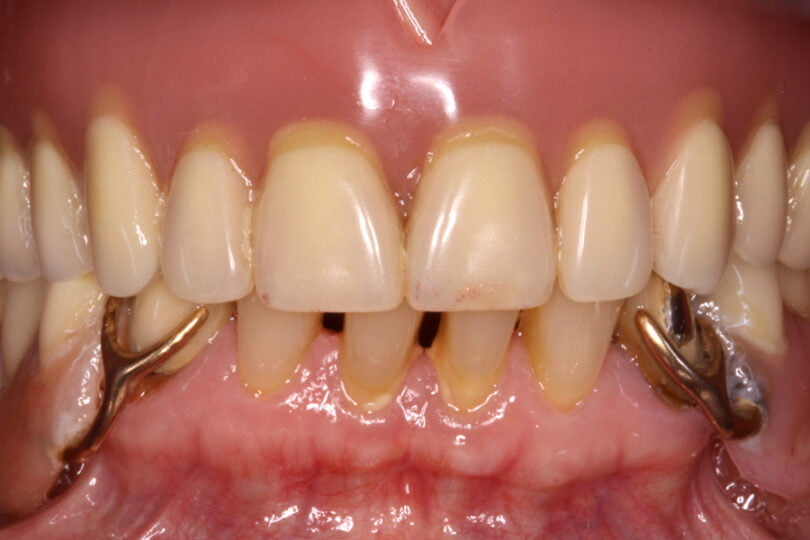

Quatro dos seis implantes foram de 5,5 mm de comprimento por 5 mm de diâmetro, um implante foi de 6,5 mm de comprimento por 3,75 mm de diâmetro e o último implante foi de 6,5 mm de comprimento por 5 mm de diâmetro (figura 2).

As seguintes imagens apresentam um dos casos incluídos no estudo (figura 03 – 15).